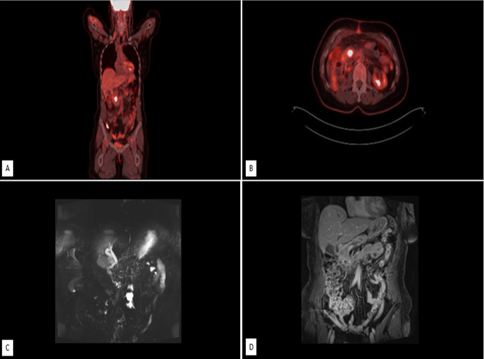

Uterine Myxoid Leiomyosarcoma Associated with Multiple Myomata in a Fertile Woman: A Case Report

Journal of Oncology Research and Therapy